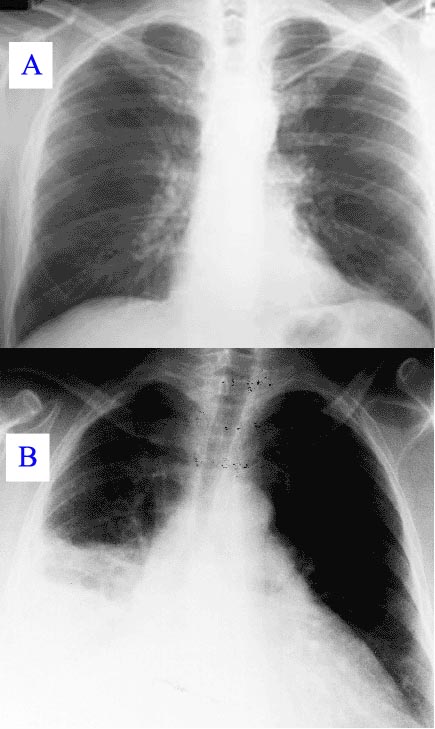

질병이 진행되면서 일부 환자에게서는 비정형 폐렴으로 발전할 수 있으며, 이는 감염 후 첫 4~5일 동안 생명을 위협하는 급성 호흡 부전 증후군(ARDS)을 유발할 수도 있다.[7] 드물게는 (육아종성) 간염이 발생하기도 하는데, 증상이 없거나 불쾌감, 발열, 간 비대, 복부 우상부 통증 등이 나타날 수 있다. 간염 발생 시 트란스아미나제 수치 상승은 흔하지만 황달은 드물다.[8] 또한 매우 드물게 망막 혈관염이 발생할 수도 있다.[8] 전체 급성 큐열 환자의 약 20% 정도에서 폐렴이나 간염 증상을 보이는 것으로 알려져 있다.